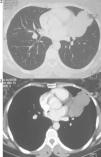

A computed tomography scan (Figs. 2 and 3) revealed a partially cystic heterogeneous mass, forming at the lingular bronchi and then developing in intrathoracic without mediastinal lymphadenopathy or pleural effusion.